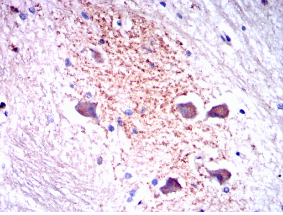

SYT1 Mouse Monoclonal antibody[8G11]

SYT1: synaptotagmin I. The synaptotagmins are integral membrane proteins of synaptic vesicles thought to serve as Ca(2+) sensors in the process of vesicular trafficking and exocytosis. Calcium binding to synaptotagmin I participates in triggering neurotransmitter release at the synapse.

IHC    1/200 - 1/1000